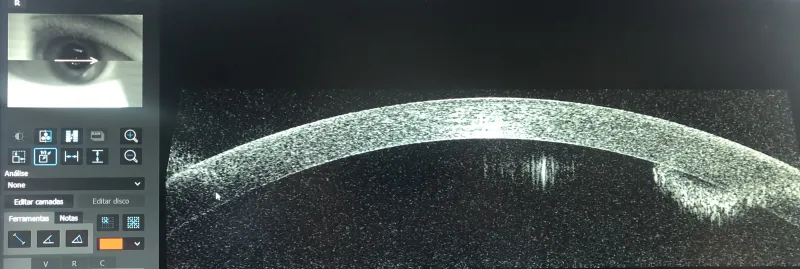

O que é a cirurgia descolamento de retina?

O descolamento de retina é uma condição ocular séria que pode levar à perda de visão se não for tratada rapidamente.

A cirurgia de descolamento de retina é um procedimento cirúrgico que visa recolocar a retina na sua posição correta, utilizando técnicas específicas conforme a gravidade e localização do descolamento.

A intervenção precoce é fundamental para aumentar as chances de recuperação visual e preservar a visão do paciente.